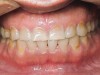

Figure 4  Indentations on tongue caused by forceful pressing of tongue on lingual surfaces. By pushing the tongue anteriorly, the airway is opened.

Figure 4